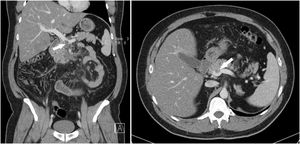

We present the case of a 40-year-old man with no history of interest who came to the emergency room due to abdominal pain in the epigastrium that had progressed over several days, with no other associated symptoms. Physical examination was anodyne, and laboratory tests showed: D-dimer 446 ng/mL, fibrinogen 742 mg/dL, and slightly prolonged prothrombin time (PT) and activated partial thromboplastin time (aPTT). SARS-CoV-2 screening was done with a polymerase chain reaction (PCR) test of a nasopharyngeal exudate sample as part of the hospital protocol, and the patient was discharged with a diagnosis of nonspecific abdominal pain. The next day, the patient received a positive PCR result for SARS-CoV-2. After 12 days of home isolation, the patient returned to the emergency room due to worsening abdominal pain and general malaise. He presented a diffusely tender abdomen with guarding and signs of peritoneal irritation in the epigastrium and mesogastrium. He did not present respiratory symptoms. Laboratory tests revealed increased acute-phase reactants. PT and aPTT remained long, fibrinogen elevated, and D-dimer increased to 947 ng/mL. Chest X-ray showed no pathological findings. A computed tomography (CT) scan was requested, which revealed a thrombus in the superior mesenteric vein originating from the confluence of the mesenteric-portal axis and a section of approximately 50 cm of dilated proximal jejunum with a thickened wall due to submucosal edema with low contrast uptake (Fig. 1). No intestinal pneumatosis, pneumoperitoneum or free fluid were observed. Given these findings, we decided to admit the patient in isolation for anticoagulant treatment and close monitoring. The patient had a good evolution, with a progressive decrease in abdominal pain, and was discharged on the sixth day after two negative nasopharyngeal exudate PCR. At discharge, a CT scan showed the resolution of the loop edema and the persistence of the thrombus. Oral anticoagulation was prescribed for six months. Four months later, a coagulopathy study revealed antithrombin III deficiency.